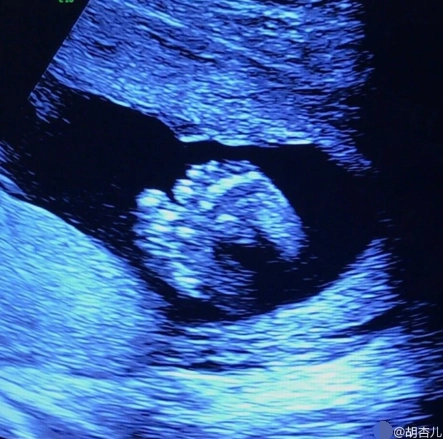

凤凰网娱乐讯 继宣布怀孕后,6月5日,胡杏儿再次晒出一张b超照,并